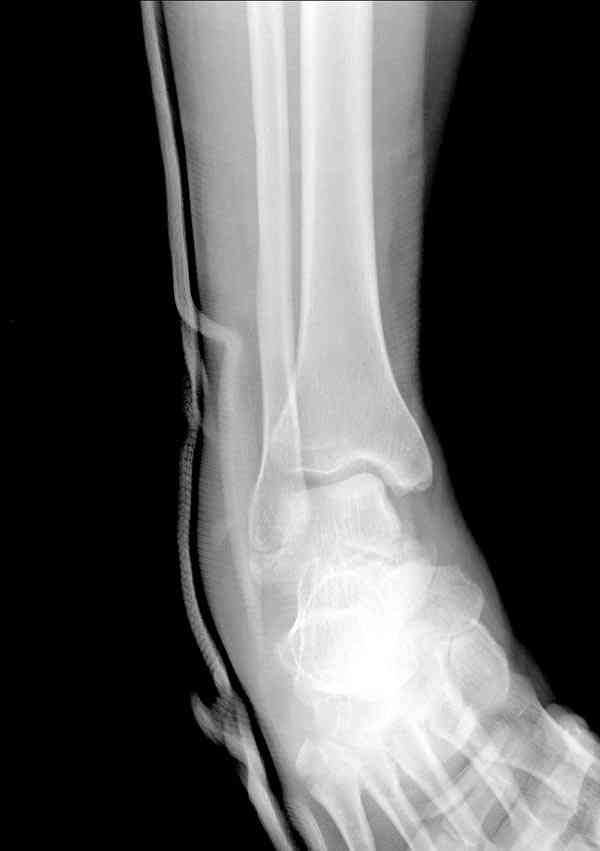

Случай с множественным оскольчатым переломом тарана оперированный из двойного доступа.

Через 2 мес.: